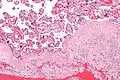

Micrograph of decidualized endometrium due to exogenous progesterone. H&E stain.

The decidua has a histologically-distinct appearance, displaying large polygonal decidual cells in the stroma. These are enlarged endometrial stromal cells, which resemble epithelium (and are referred to as "epithelioid").

Decidualization includes the process of differentiation of the spindle-shape stromal fibroblasts into the plump secretory decidual cells, which create a pericellular extracellular matrix rich in fibronectin and laminin (similar to epithelial cells).